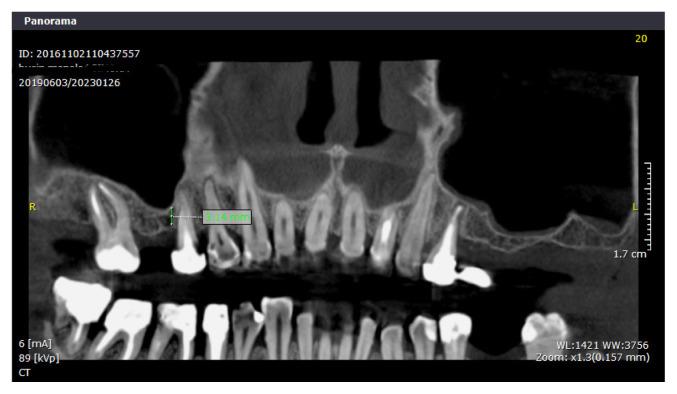

Much of the research published involves using artificial products, like xenografts and resorbable collagen membranes, after a prior Cone Beam Computer Tomography (CBCT) investigation. Nowadays, more accessible access, less financial costs, a biological approach, and faster healing are objectives that surround this procedure. Leucocytes and platelets rich in Fibrin (L-PRF) are a natural component with a high concentration of growth factors. Due to its regenerative properties and lack of complications, it is used in several medical fields, like orthopedics, dermatology, and oral surgery. This retrospective study aims to compare results in bone height and volume obtained through external sinus lift, either by using xenografts or autologous plasma rich in fibrin, by evaluating the quantity of new bone formation from a radiological point of view.

Fifty-eight Caucasian patients were included in this retrospective study; 48 were submitted to xenograft procedure, and 10 were selected for L-PRF grafting material with simultaneous implant placement. Lack of clinical and histological studies performed on patients with L-PRF surgeries limited us in choosing a larger group for the radiological analysis. CBCT evaluation was performed before surgery and 6 months after. All patients selected for the study presented good general and oral health, acute oral and sinus infections excluded; smoking and periodontal disease were also criteria of exclusion. Two operators performed the measurements in pre-established landmarks in different time frames. The two independent groups were compared with the Wilcoxon rank-sum test for quantitative data. Qualitative characteristics were described as counts and percentages. All analyses were performed in an R environment for statistical computing and graphics.

Mean bone height gain in the xenograft group in the regions was as follows: 7.44 for the anterior landmark, 12.14 for the median and 8.28 for the distal. The mean group height gained for the L-PRF group was 0.1 anteriorly, -0.18 for the median measurement, and 0.23 distally. We obtained excellent overall reliability for all the height measurements between the two operators.